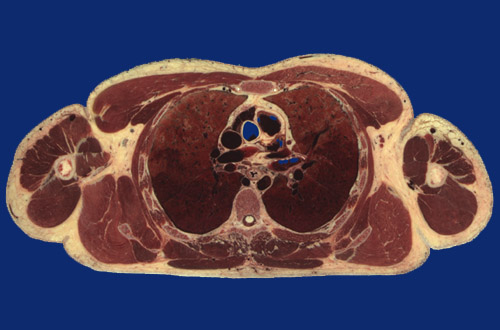

Identify the following regions in the image above: Pectoralis major - Pectoralis minor - Biceps brachii - Deltoid - Triceps brachii (long & lateral heads) - Triceps brachii (medial or short head) - Humerus - Scapula - Triangle of auscultation - Latissimus dorsi - Teres major - Subscapularis - Rhomboid major - Sacrospinalis - Transversospinalis - Trapezius - Serratus anterior - Body of sternum - Internal thoracic vessels - Cephalic vein - Pulmonic trunk - Ascending aorta - Superior vena cava - Right pulmonary artery - Left pulmonary artery - Bronchus - Right upper lobe - Right lower lobe - Left upper lobe - Left lower lobe - Left atrium - Esophagus - Descending aorta - Vertebral body - Spinal cord